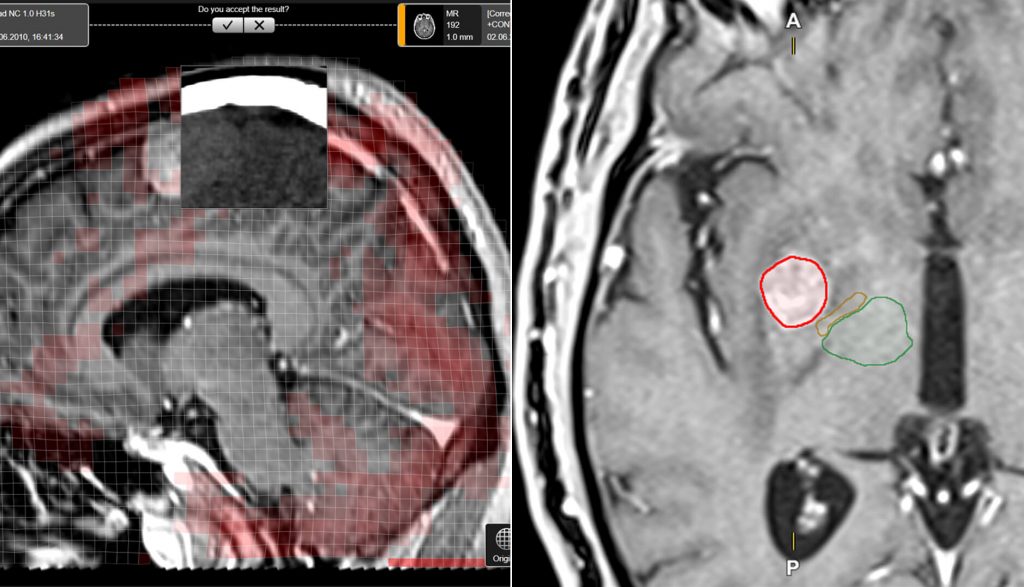

Radyocerrahi Uygulama Yazılımında

Otomasyon

& Standardizasyon

Çoklu Beyin Metastazı